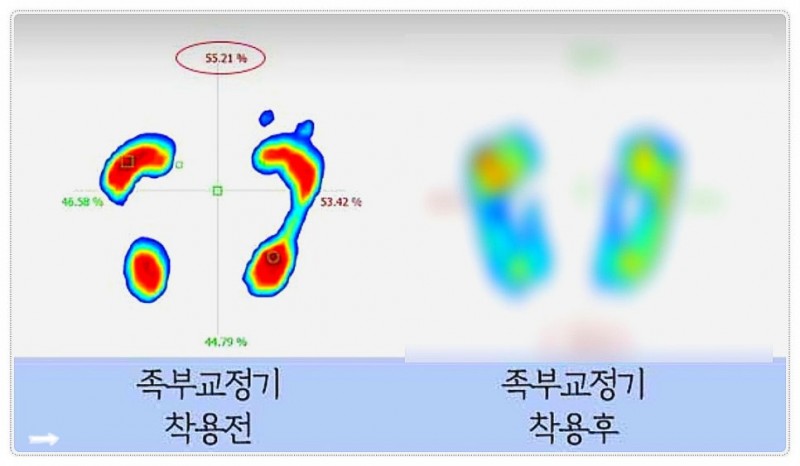

여기서 한 발 더 나아가 여러분의 발바닥에 주목해 볼까요?

우리 몸의 주춧돌인 발이 무너져 있으면 아무리 허리를 맞춰놔도 금방 다시 틀어지게 됩니다.

그래서 개개인의 보행 특성을 분석해 '맞춤형 기능성 깔창(족부교정기)'을 활용하는 거죠.

걷는 자세부터 바로잡아 허리로 가는 충격을 발바닥에서부터 흡수해 주니 치료 효과가 지속되는 데 도움을 줄 수 있답니다.